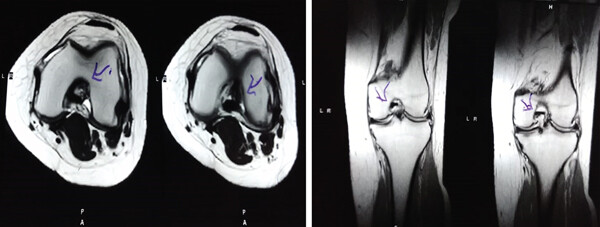

MRI檢查發(fā)現(xiàn)半月板損傷處修復(fù):3D MRI 顯示 2 年時半月板撕裂難以辨別。

結(jié)論:滑膜間充質(zhì)干細(xì)胞移植后,2年的隨訪中,患者的關(guān)節(jié)功能改善,MRI檢查發(fā)現(xiàn)半月板損傷處恢復(fù),沒有發(fā)生導(dǎo)致研究終止的重大不良事件。可以達(dá)到干細(xì)胞治療半月板損傷長期療效的目標(biāo)。

影像學(xué)檢查:4例MM皮瓣撕裂患者在治療前后交界區(qū)中央?yún)^(qū)域出現(xiàn)缺損,但其中2例患者該區(qū)域完全恢復(fù)穩(wěn)定光滑狀態(tài),另2例患者該區(qū)域部分恢復(fù)。治療前后交界區(qū)中央?yún)^(qū)域皮瓣撕裂的關(guān)節(jié)鏡評分為0.3±0.5,治療后為4.3±2.1,治療后評分顯著升高。2例患者原有放射狀MM撕裂在治療一年后愈合。

關(guān)節(jié)功能:治療后4周和52周的Lysholm評分顯著高于治療前。

結(jié)論:間充質(zhì)干細(xì)胞移植后,隨訪24個月內(nèi),患者影像學(xué)和關(guān)節(jié)功能顯著改善,未發(fā)生嚴(yán)重不良事件。可以達(dá)到干細(xì)胞治療半月板損傷長期療效的目標(biāo)。